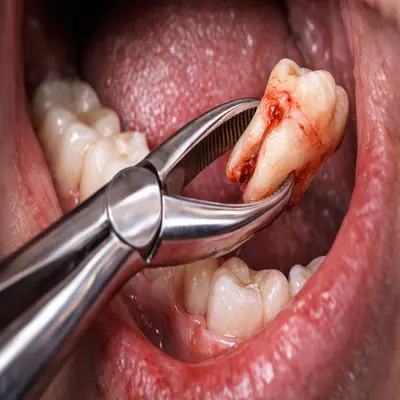

کشیدن آسان دندان عقل با فورسپس و بیحسی کامل داخل دهان